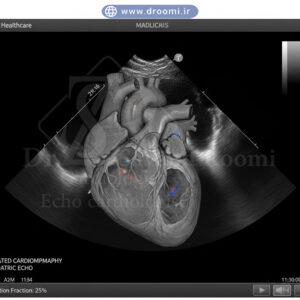

اکو قلب کودک مبتلا به کاردیومیوپاتی اتساعی با نمایش کاهش عملکرد قلب

کاردیومیوپاتی و مشکلات عملکرد قلب در اطفال

هرچند کمتر شایع از نقصهای ساختاری، کاردیومیوپاتیها (بیماریهای عضله قلب) مانند کاردیومیوپاتی دیلاته یا هیپرتروفیک نیز در کودکان دیده میشوند. این بیماریها ممکن است مادرزادی، خانوادگی یا ثانویه به عفونتها و متابولیک باشند.

اکوکاردیوگرافی کودکان شیراز با ارزیابی دقیق اندازه حفرات قلب، ضخامت دیوارهها، کسر جهشی (EF) و الگوهای حرکت دیواره، این مشکلات عملکردی را تشخیص میدهد. داپلر بافتی و استرِین تصویربرداری نیز در مراکز پیشرفته برای ارزیابی دقیقتر عملکرد میوکارد استفاده میشود. تشخیص زودهنگام این بیماریها با اکو قلب رنگی اطفال میتواند جان کودک را نجات دهد و درمان دارویی یا حتی پیوند قلب را بهموقع برنامهریزی کند.